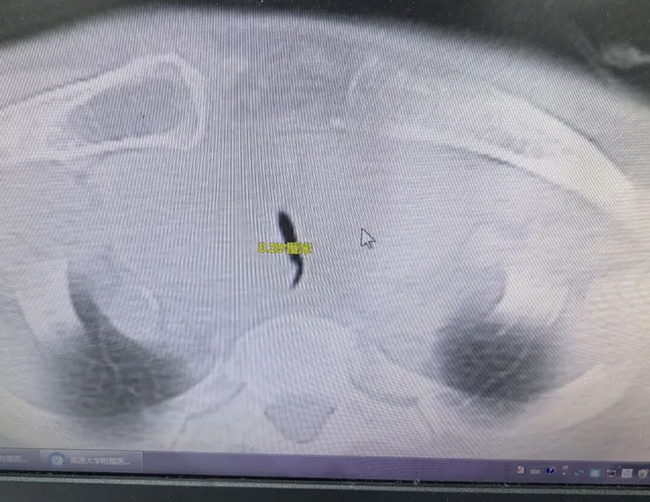

患者为76岁老年女性,因突发严重呼吸困难,经120急救送入急诊科。检查发现,其胸骨后方存在巨大甲状腺肿物,气管受严重压迫,最狭窄处仅约2.9毫米(相当于三根耳钉并排宽度),受压长度达64.2毫米,气道几乎闭塞,患者随时面临窒息危险。

图为2.9毫米狭窄区域